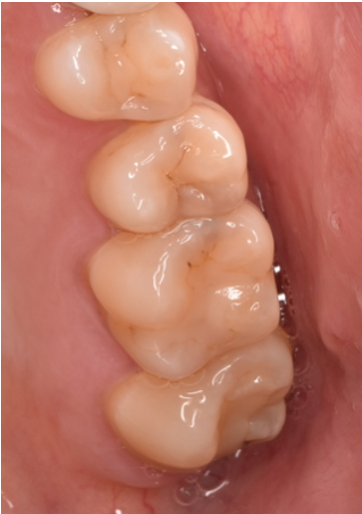

セラミック 2022.1260代男性「銀歯を全部白いものに変えたい」銀歯をE-maxインレー、フルジルコニアインレー・クラウンで白く変更した症例